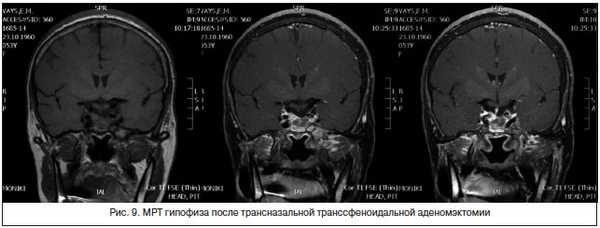

Оперативное вмешательство проведено нерадикально, больная была направлена на стереотаксическую радиохирургию. До момента проведения лучевой терапии на область гипофиза и после нее, до развития эффекта от проведенного лечения, больной рекомендовано продолжить терапию Октреотидом-депо в дозе 40 мг 1 раз в 28 дней.

В 2017 г. мы проанализировали результаты МРТ головного мозга 180 больных, включенных в регистр. Микроаденома выявлена у 22,8% больных, макроаденома - у 55,8%, «пустое турецкое седло» - у 2,8%, состояние после оперативного вмешательства на гипофизе / лучевой терапии - у 18,6%.